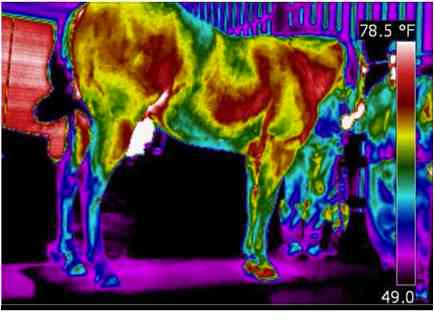

TheraPlate Imaging

One of the primary therapeutic mechanisms of the TheraPlate is increasing circulation, both immediately and long-term. The short-term impact can be seen via thermograms. Here we see "Buck" imaged before and during a session on the TheraPlate. Notice the significant increase in skin temperature across much of his body, particularly those areas with large muscle mass. This can be attributed to the increased blood flow to those areas as the muscles react to the motion of the TheraPlate.